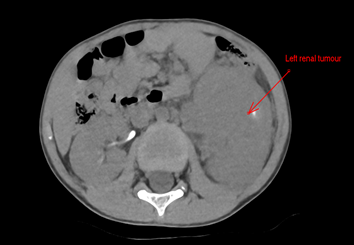

Paciente masculino, 6 anos, 21,6 kg, asmático, em tratamento com budesonida e salbutamol, alérgico a corantes, portador de volumosa massa heterogênea em rim esquerdo, com diagnóstico de tumor de Wilms não metastático com trombo tumoral em veia cava inferior (Figura 1).

Figura 1. Tumor renal esquerdo pré-quimioterapia